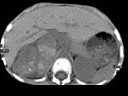

男孩,5岁。消瘦、贫血、纳差和腹部包块3个月余, CT如图所示,下列说法正确的是

A、右侧腹腔内可见一巨大软组织肿块影,其边界欠清楚

B、肿块密度不均匀,可见片状的较高密度,考虑为出血,也可见点状的钙化影

C、该病灶来源于肝脏,考虑为肝母细胞瘤

D、该病灶来源于右肾上腺,考虑为神经母细胞瘤

E、该病灶来源于右肾,考虑为肾胚胎瘤